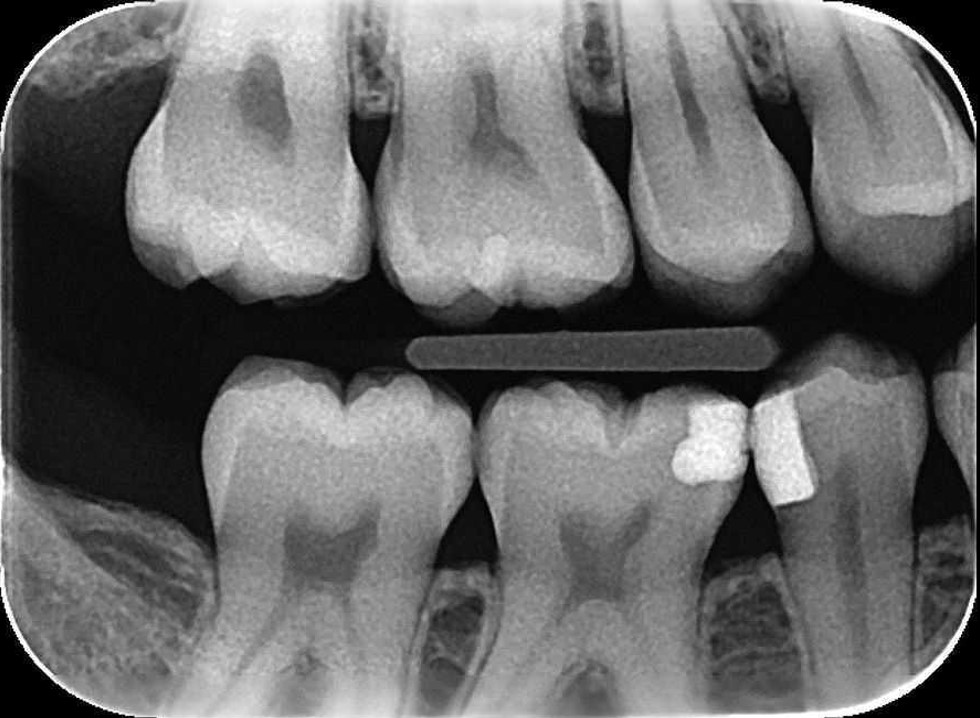

RADIOGRAFÍA INTERPROXIMAL

(ALETA DE MORDIDA)

Esta radiografía se utiliza para examinar las superficies interproximales de los dientes, incluidas coronas de dientes superiores e inferiores, áreas interproximales y del hueso de la cresta alveolar. Con la finalidad de detectar caries interproximales, evaluar adaptación de restauraciones y valorar el estado de la cresta ósea.

En sus principales indicaciones se encuentran:

Evaluación de lesiones cariosas interproximales

Evaluar el estado de restauraciones interproximales

Evaluación del estado periodontal

Monitorear el avance de lesiones cariosas interproximales

Ventajas:

una ventaja importante es que se puede evaluar las coronas superiores e inferiores de molares o premolares en una sola toma; otra ventaja es que se puede tomar verticalmente para observar las crestas oseas superiores e inferiores.